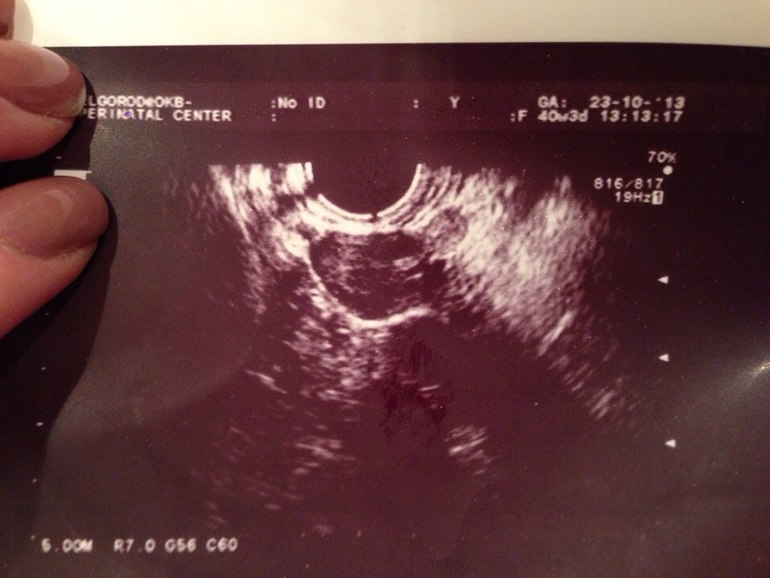

в прошлом месяце была зб с верхним показателем хгч 107,потом падал,нижний показатель был 36,дальше не отслеживала,23 пришли месячные,3-го на узи эндометрий 2 мм и предполагаемая овуляция через 5 дней,пила дюфастон с 15 по 25 дц,на 25 дц сделала тест на Б,две полоски,хгч 94,5,через 2 дня 74,в клинике "Маханова" ничего не увидели,эндометрий 2 мм и как только мес прошли картина,позвонила своему врачу-говорит не может быть всё так чисто,пошла на узи по знакомству сегодня днём,в итоге увеличена левая труба

врач сказала,что эмбриона она не видит,пересдать хгч и к ней на операцию,трубу сказала удалять и сохранять смысла нет!а как не сохранять если она последняя у меня !

)хгч сдаю завтра,я почти уверенна,что ВБ,всё просто сходится,а узи буду делать у неё,она очень хорошая узистка,в другой клинике не увидели увеличения,аппарат более слабый,спасибо,буду надеяться,что сохранят трубу...